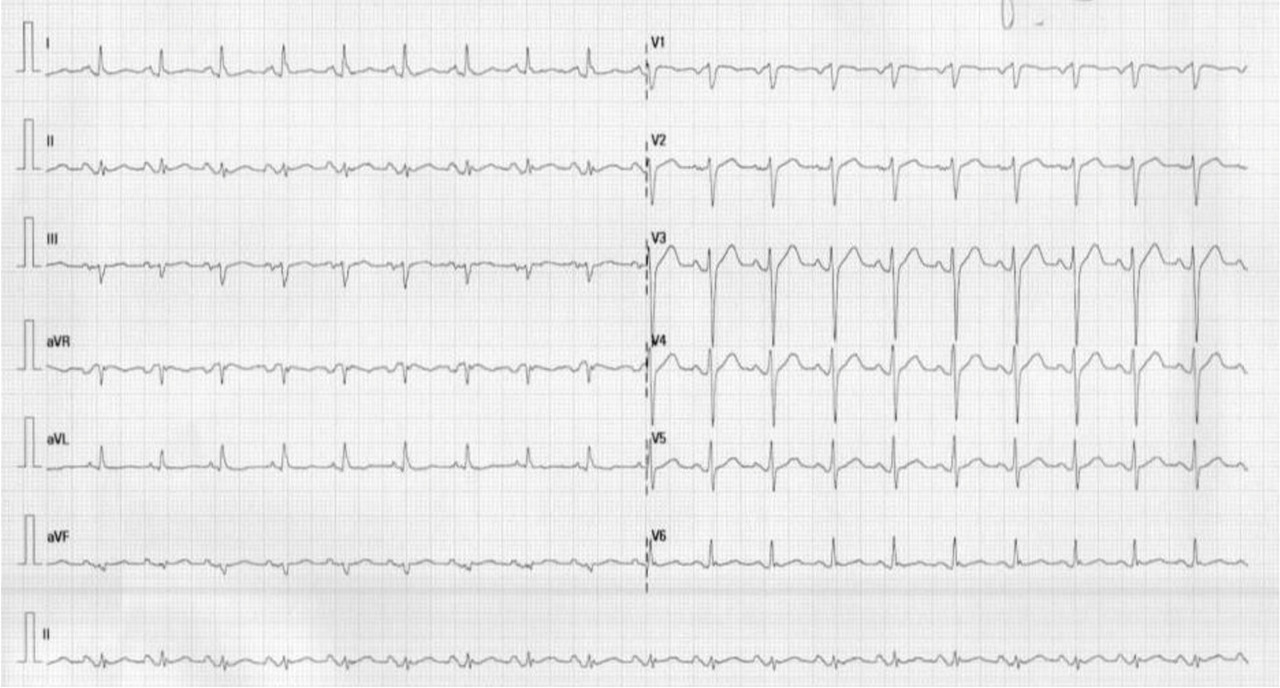

Encadré rouge : le VEMS/CVF ou VEMS/CVmax (= rapport de Tiffeneau) permet de déterminer s’il existe un trouble obstructif ou non.

À noter que la CVmax peut être différente de la CVF (F pour forcée), pourquoi ?

La CVmax correspond à la capacité vitale la plus grande parmi la CVL et la CVF.

Chez les patients très obstructifs, la réalisation d’une spirométrie engendre un collapsus des bronches du fait de la baisse de pression rapide dans les bronches. En comparaison à la réalisation de la CVL (L pour lente) lors de la pléthysmographie, ce qui permet de garder les bronches ouvertes.

En conclusion, chez les patients très obstructifs, on peut observer une différence entre la CVL et la CVF (généralement CVL > CVF).